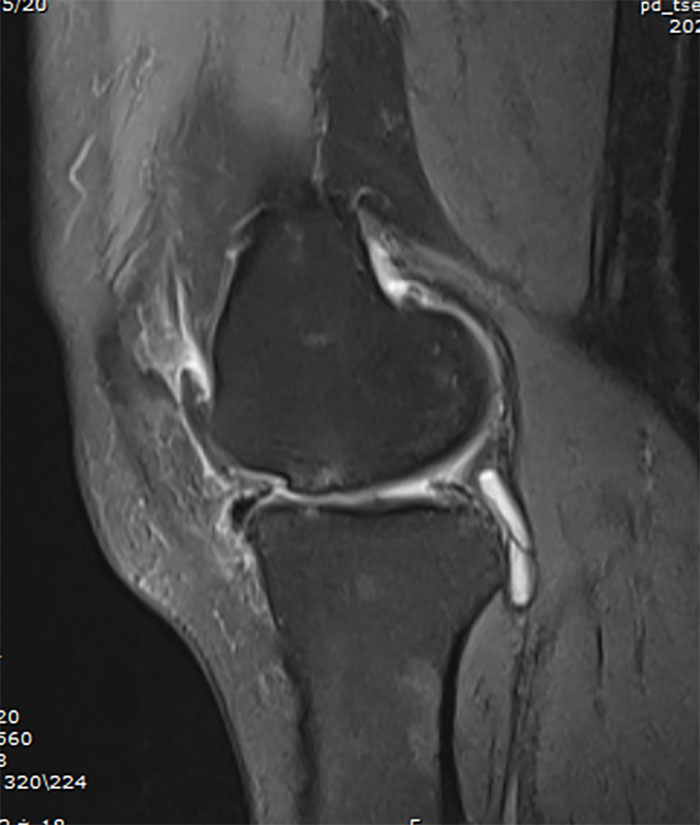

關節(jié)外一科(骨四科)主任白玉明接診后,仔細詢問病史,并進行查體及對影像學資料的審閱,診斷為右膝(內側)單間室骨性關節(jié)病、內側半月板撕裂伴外突。MRI顯示:右膝內側間室軟骨明顯磨損變薄,基本是骨磨骨狀態(tài),并伴隨軟骨下骨骨髓水腫。

以往傳統(tǒng)治療膝骨性關節(jié)病的方式是全膝關節(jié)置換(TKA),對比于單髁關節(jié)置換,全膝關節(jié)置換創(chuàng)傷大、恢復慢、本體感覺差,考慮患者右膝髕股關節(jié)及外側間室無明顯疼痛癥狀,且MRI顯示:外側半月板、軟骨及前交叉韌帶基本完好,膝關節(jié)屈伸功能無受限,關節(jié)外一科(骨四科)手術團隊為患者選擇了膝關節(jié)單髁置換(UKA),在征得患者及家屬同意后,制定了詳細周密的手術方案。